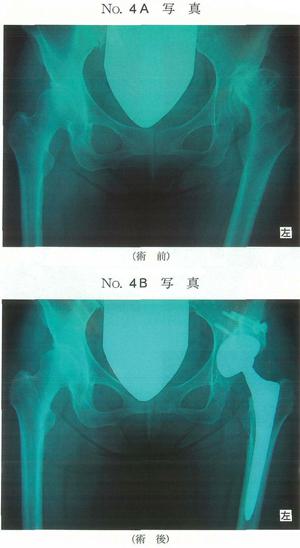

第42回 午前

58歳の女性。先天性股関節脱臼で小児期にリーメンビューゲル装具で加療した。10年前から歩行時に左股関節痛があった。痛みは進行し、1年前から杖が必要となり、靴下の着脱も困難となったため手術を受けた。股関節の術前と術後のエックス線単純正面像(別冊No.4A、B)を別に示す。左股関節の術前エックス線写真の所見で認められないのはどれか。

1

骨嚢胞

2

骨棘形成

3

関節裂隙狭小化

4

臼蓋形成不全

5

内反股